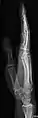

- Radius and Ulna - AP and Lateral

- Fingers - DP and Lateral

- Thumb - AP and Lateral